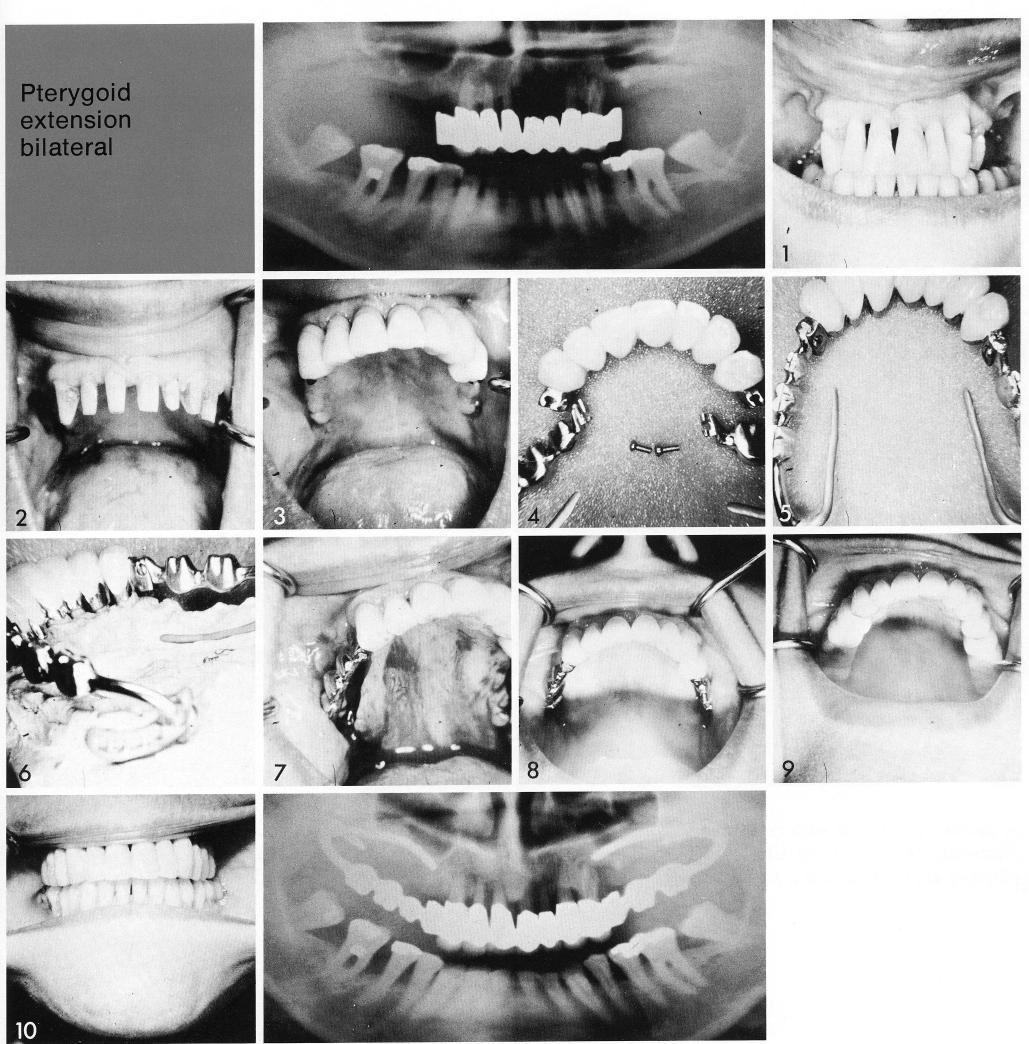

Pterygoid extension bilateral

Male and female attachments were also used in old style bilateral pterygoid extension implants. Here the natural tooth situation was stabilized (1,2), and an anterior splint prepared (3). This had cantilevered female attachments (4) for accepting the male attachments of the pterygoid extension implants (5). Note that the old style implants (6) are characterized by a bar arising from the hamular notch; long, thin palatal arms embracing the tuberosity, and by horizontal screws to further insure anterior lockage. The implants were inserted (7,8), and the case finished when their respective splints were cemented (9,10).

1 Male and female attachments in bilateral pterygoid extension implants